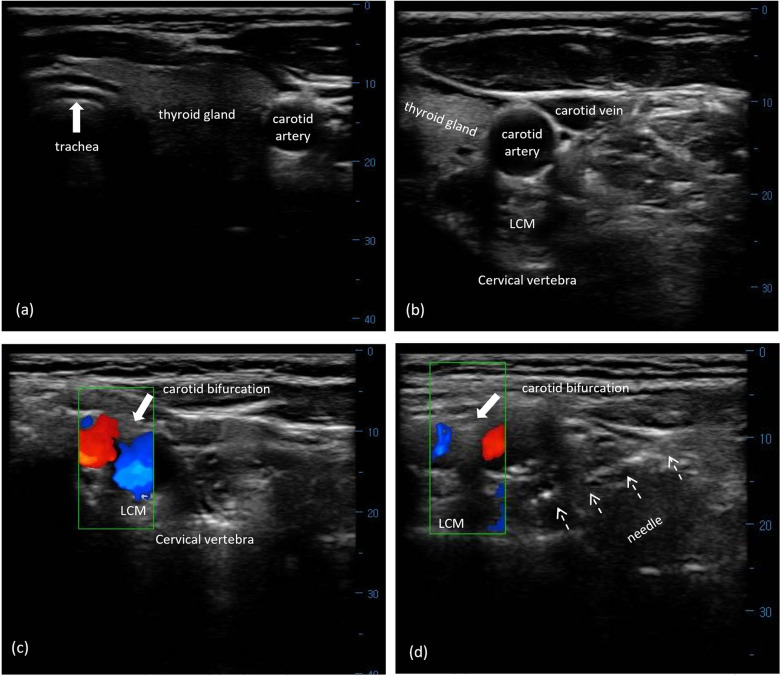

Background: This study aimed to examine the efficacy and safety of ultrasound (US)-guided superior cervical ganglion (SCG) block in conjunction with standard triptan in the management of migraine attacks.

Methods: In total, 243 subjects who received an adjunctive US-guided SCG block alongside triptan for a migraine attack were enrolled as the SCG cohort. A 1:1 propensity score based on baseline covariates was used to match 243 cases who received triptan alone as the control. The primary endpoints were pain relief and freedom from pain within 24 h after the procedure. Secondary outcomes included headache relief and freedom from pain within 2 h, monthly migraine days (MMDs), Migraine Disability Assessment (MIDAS) scores, Migraine-Specific Quality of Life questionnaire (MSQ) scores, and adverse events.